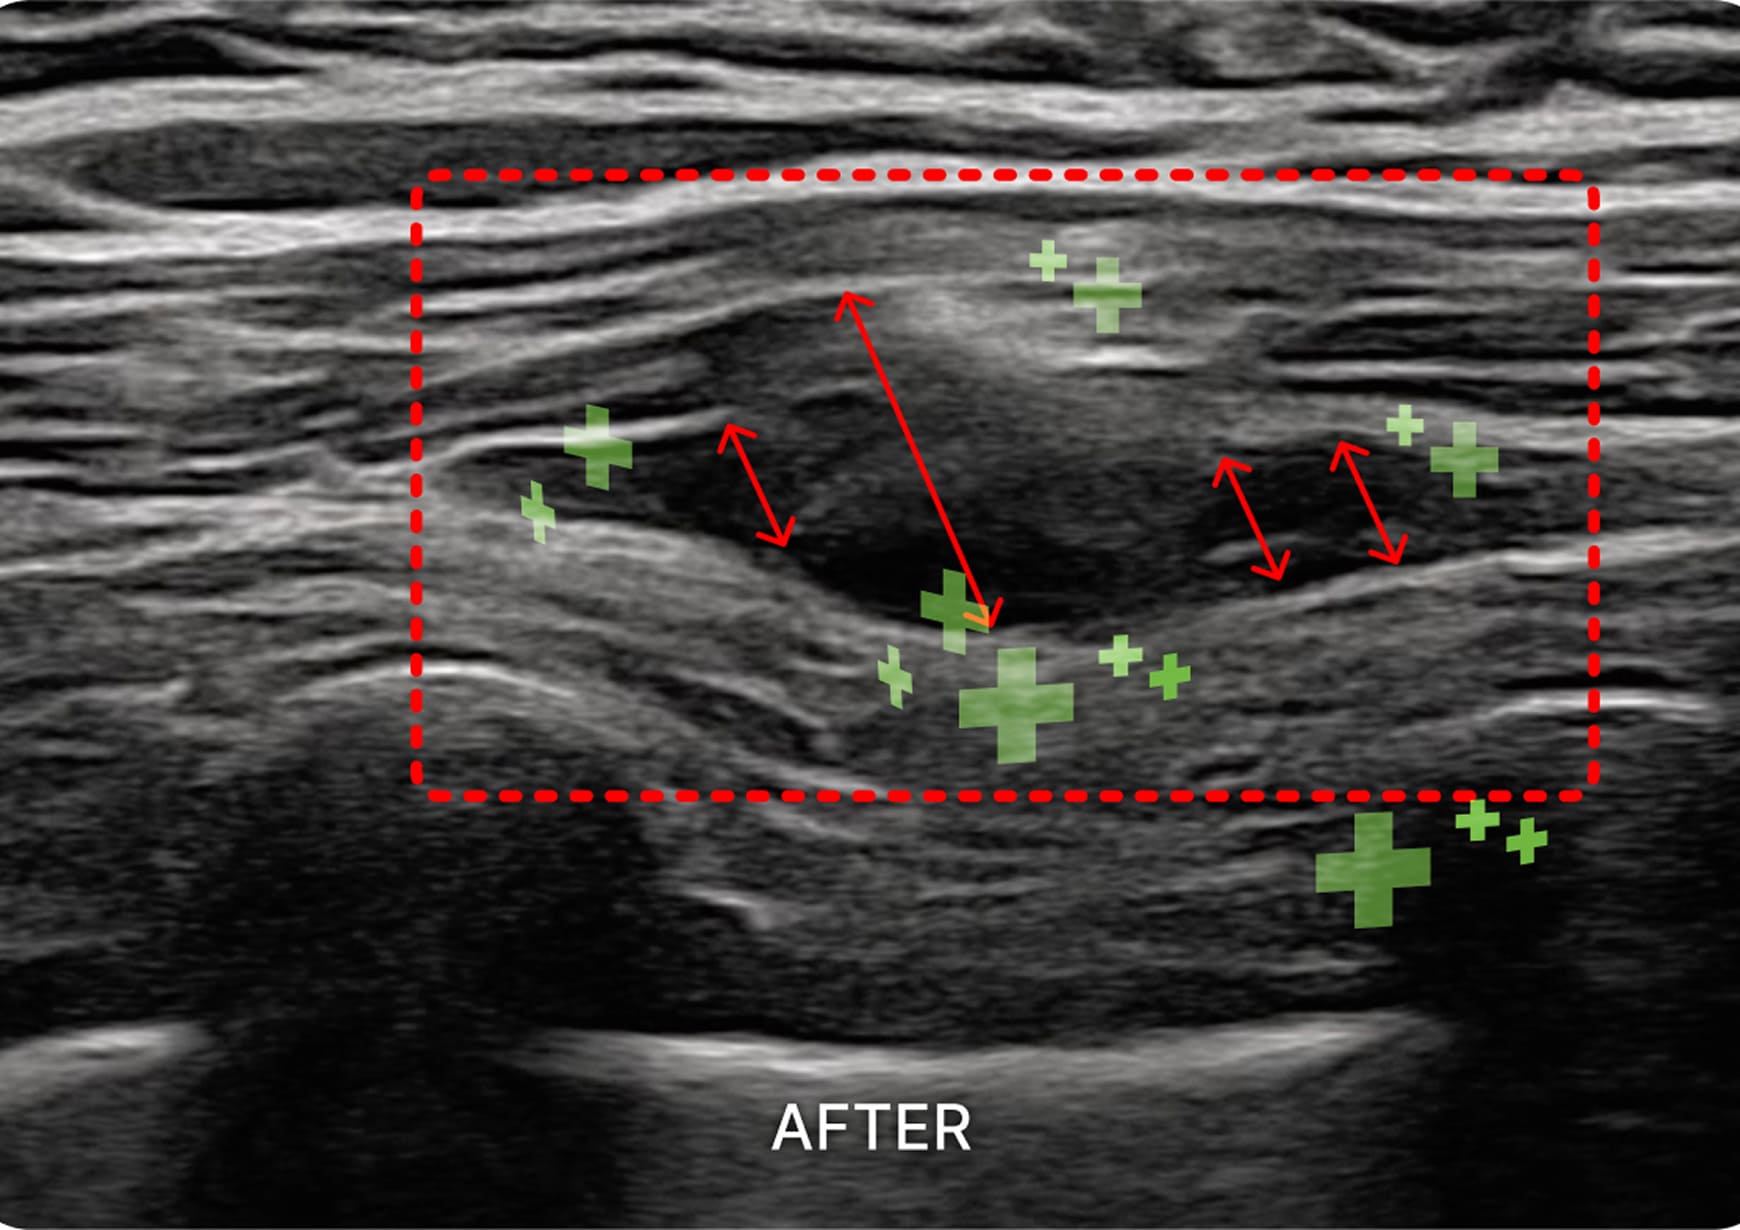

초음파 검사

1. 초음파 시술

초음파를 활용하여 근육과 신경 문제를

정확히 진단하고 치료하여 통증과 기능

이상을 개선하는 시술입니다.

흉추다열근

교감 신경의 과항진에 따른 심장 두근거림, 소화기 연동 운동 장애

간담도 이상, 부신 기능 저하 등의 허혈성 상태를 개선합니다.